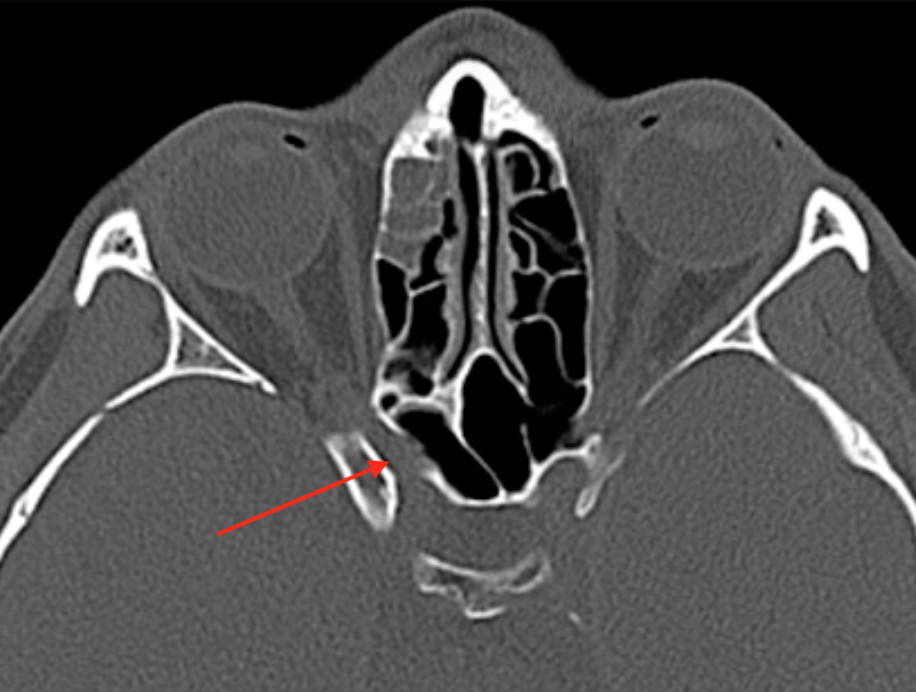

Stylomastoid foramen

• Facial nerve exits the base of the temporal bone through tstylomastoid foramen

• Only motor portion of CN7 exits the stylomastoid foramen